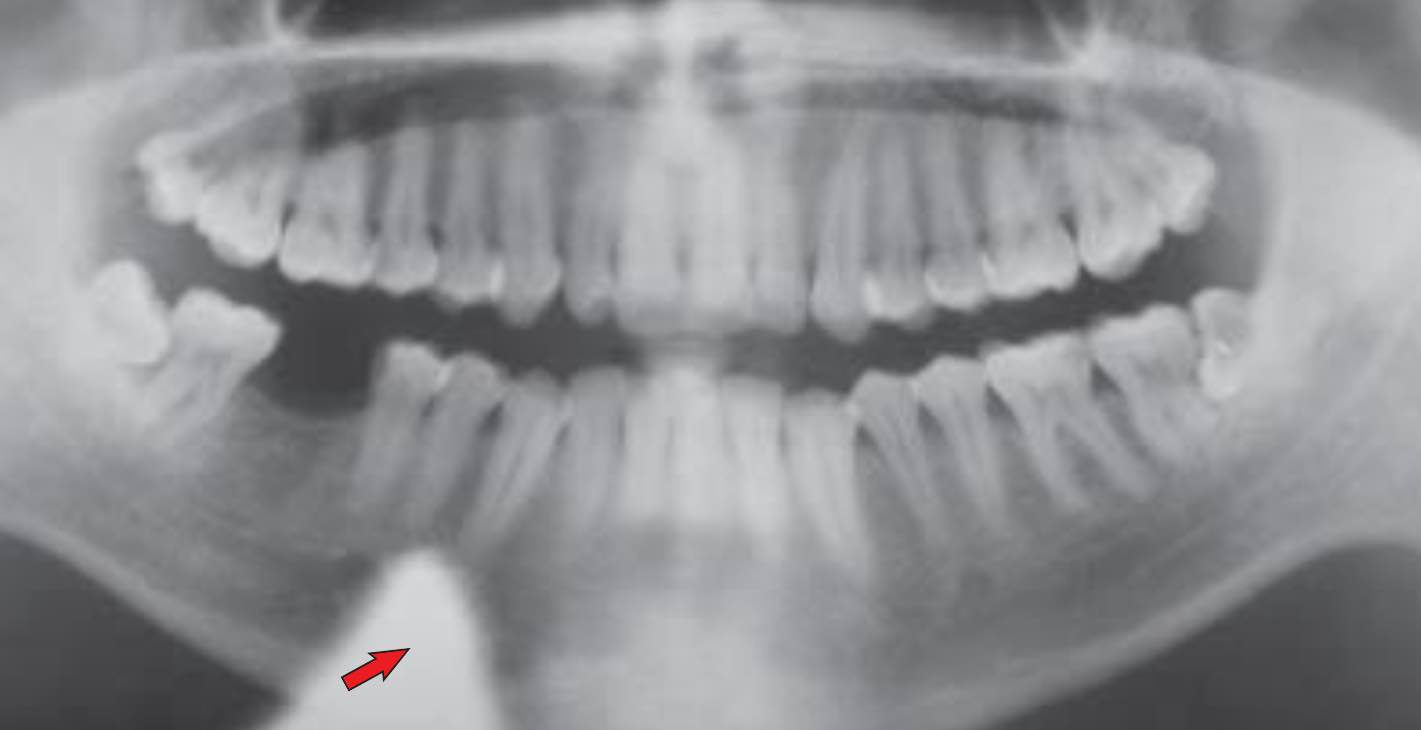

⚠️ Pormenores pobres na região apical anterior, incisivos inferiores difusos

⚠️ Ausência de côndilos na imagem radiográfica

⚠️ Linha de sorriso exagerada ou tipo bico de ave

Estes erros ocorrem devido a uma situação oposta à anterior, ou seja, o paciente tem o plano de Frankfurt inclinado para baixo e a solução, claro, é a mesma que a anterior, para posicionar correctamente o plano paralelo ao solo.

Imagen 4: Linha do sorriso exagerado